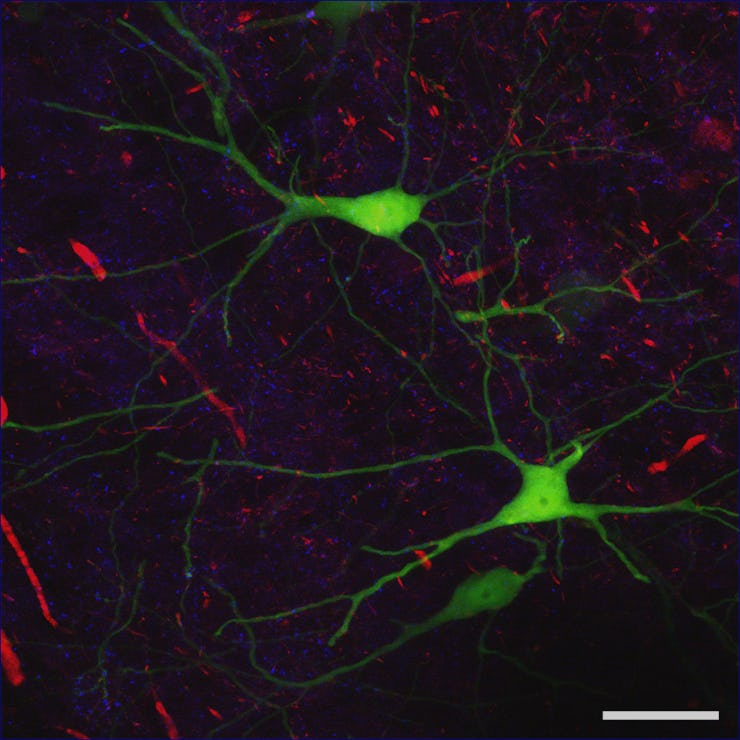

Why do we feel lonely?

There’s loneliness, the kind you get when you’re 8 hours into a solo Wet Hot American Summer marathon and haven’t heard from a single soul, and then there’s loneliness, the soul-crushing, life-consuming kind that spawns the world’s guitar-toting Justin Vernons. Here’s a neurological explainer of that second thing.